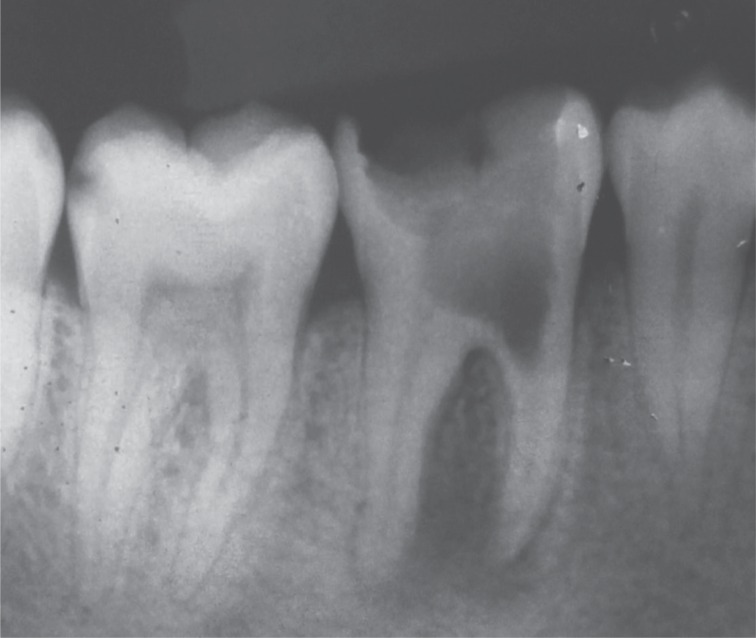

9). The patient returned for follow-up after 6, 12, and 20 months, and the radiographs revealed appreciable healing in the periapical area (

Figures 10,

11,

12,

13).

Figure 10Six month follow-up radiograph.

Figure 11One year follow-up radiograph showing appreciable healing in the periapical area.

Figure 12Twenty month follow-up radiograph.

Figure 13Clinical view after one year.